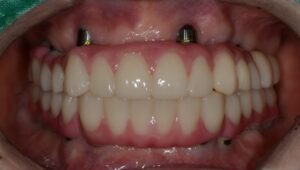

최종적으로 환자분의 풀아치임플란트가

마무리되고 난 후 사진입니다.

다수의 치아가 하나의 보철물로 제작되었지만

오차 없이 제작되어 교합이 잘 맞았어요.

환자분께서는 치료 전 상태보다 훨씬 심미적이며,

식사할 때도 불편함이 없다고 좋아하셨어요.